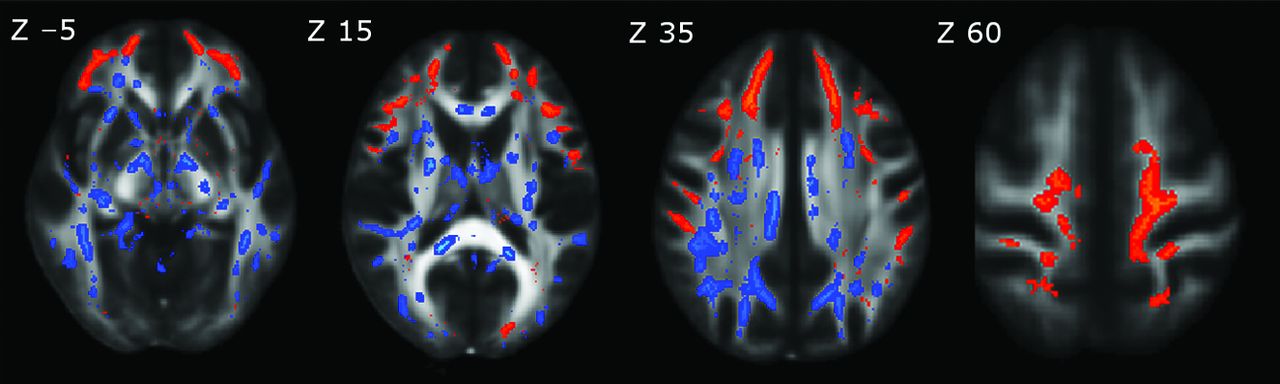

The magnitude and topographic pattern of significant changes in multiple DTI indices were not equivalent. To address this issue, we created a conjunction map of FA and RD changes. Anterior frontal structures showed a reduction in FA, without significant changes in RD, while posterior supratentorial brain regions and the brain stem showed a pre-eminent increase in RD compared with FA changes (Fig 2).

Conjunction map of spatial differences between reduced FA and increased RD maps, represented in the FMRIB58_FA template on the axial plane with Montreal Neurological Institute 152 coordinates (in millimeters) above each upper row image. Red-yellow represents decreased FA; blue-light blue, increased RD. A decrease in FA alone shows an anterior frontal circuitry pattern, while an increase in RD is more prominent in the posterior supratentorial brain regions and brain stem.

The next interesting finding emerging from our study is the inconsistency in spatial overlapping of FA and RD changes. Although both DTI indices were diffusively altered, in the conjunction map of the decreased FA and increased RD, an anteroposterior pattern was detected (Fig 2): The anterior WM seemed more susceptible to FA changes; meanwhile, the posterior supratentorial brain regions and brain stem were more prone to RD changes. Because the FA metric is a function of all 3 eigenvalues of the diffusion tensor, concurrent changes in parallel and perpendicular diffusivities may reduce the sensitivity of FA in the posterior brain regions. Mild microstructural alterations of the minor fibers and subtle disruption of the frontal lobe connections solely may lead to a decrease of FA in the anterior frontal circuitry.35 However, the neurobiologic substrate and neuropsychological correlates of these topographic discordances need to be further elucidated.